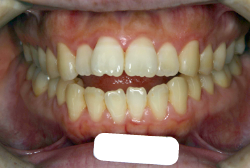

「歯並びの凸凹を直したい」という主訴で来院したケースです。診断の結果、たしかに「叢生」という隙間が足りないと言うことが原因の凸凹症例でした。

しかし、それ以上に問題なのは「前歯の噛み合い方が深すぎる」という症状で、初診の歯の正面写真を見ると下の前歯が全く見えません。こういう症状を矯正学では「過蓋咬合(かがいこうごう)」と言います。過蓋咬合を放置すると、将来的に顎関節に悪影響を与えるとされており、顎関節症の原因因子の一つです。また下の前歯の先端が、上の前歯の裏側の歯茎と強く接触するため、歯周病の原因にもなります。

検査の結果、凸凹が軽症なため非抜歯で矯正すること可能と判断、マルチブラケット装置にて治療しました。治療後は歯並びが綺麗になっただけでなく、噛み合わせ的にも正しい状態が確立しています。